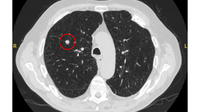

Computed tomography (CT) showing a small peripheral triangular nodule in the right lower lobe, consistent with an intrapulmonary lymph node

From the collection of Dr George Tsaknis, MD, PhD, FRCP(London), MRQA, MAcadMEd, PGCert; used with permission